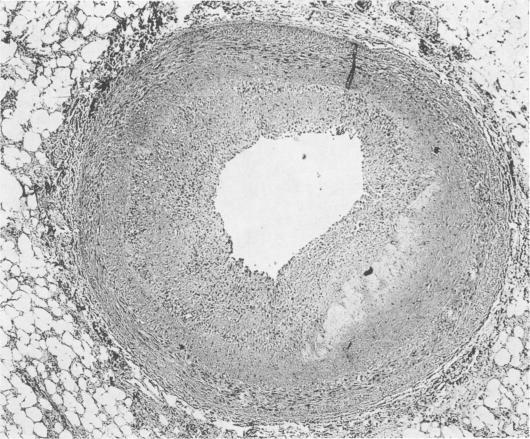

Cardiac transplantation: general considerations and results.

Ann Surg. 1969 Jun;169(6):892-905. doi: 10.1097/00000658-196906000-00009.